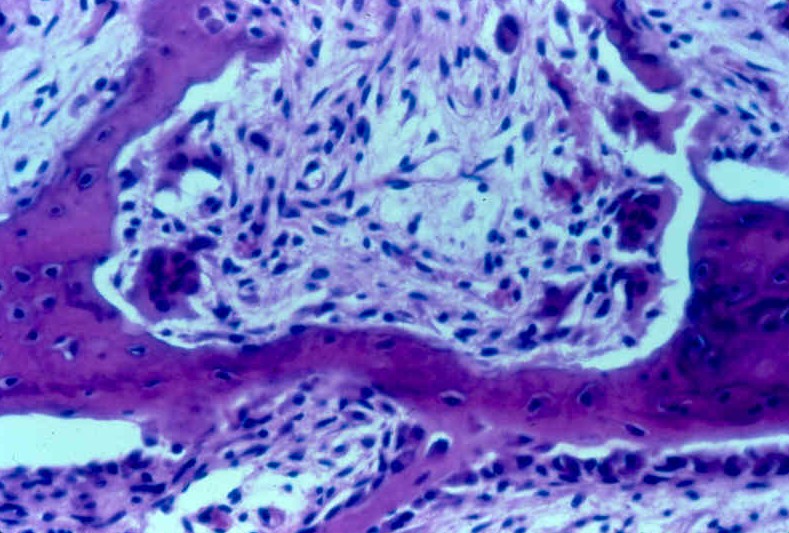

what is this

Epiphysis spongy bone

ridges of spongy bone

Traebcular

What are the spaces between ridges called?

Intertrabeculae Spaces/Pours